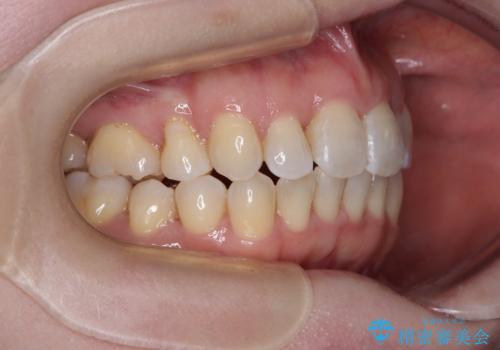

- 上下前歯のデコボコと、上顎の八重歯を気にして来院された患者様です。

下顎に対して上顎が前方にあり、第一大臼歯による咬合状態は上顎前突であったため、上顎のみ左右の第一小臼歯を抜歯し、ワイヤー装置にて矯正治療を行うこととしました。